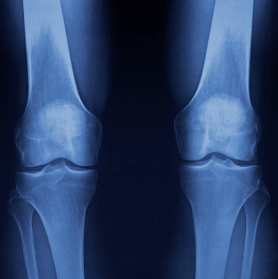

4. 무릎 연골 손상은 어떻게 확인할까? (자가 체크도 가능해요)

병.원 진단이 제일 정확하지만, 집에서도 어느 정도 체크는 해볼 수 있어요.

이런 증상이 2주 이상 지속되면 확인이 필요해요

계단에서 통증이 계속된다

무릎이 자주 붓는다

무릎이 걸리거나 잠기는 느낌이 있다

특정 각도에서 찌릿한 통증이 반복된다

걷는 거리가 줄어들 정도로 불편하다

특히 무릎이 “잠기는 느낌”, “갑자기 안 펴짐”, “붓기 반복”은 그냥 근육통이 아닐 수 있어요.